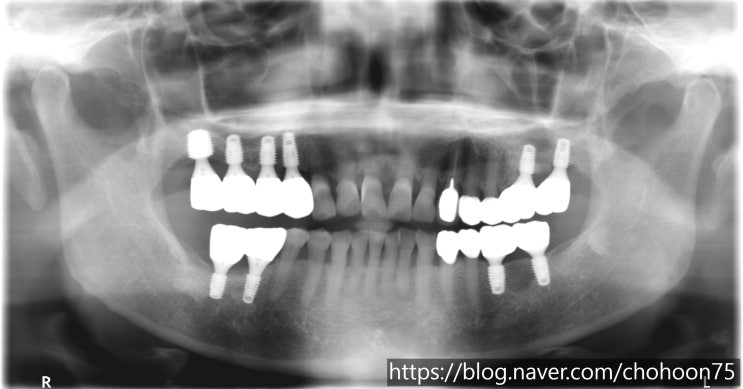

[조훈치과] 발치 즉시 임플란트 식립 치료 증례

안녕하세요. 조훈 치과입니다. 오늘은 앞서 2018년 7월, 조훈 치과 블로그에 포스팅하였던 치료 증례로 최...